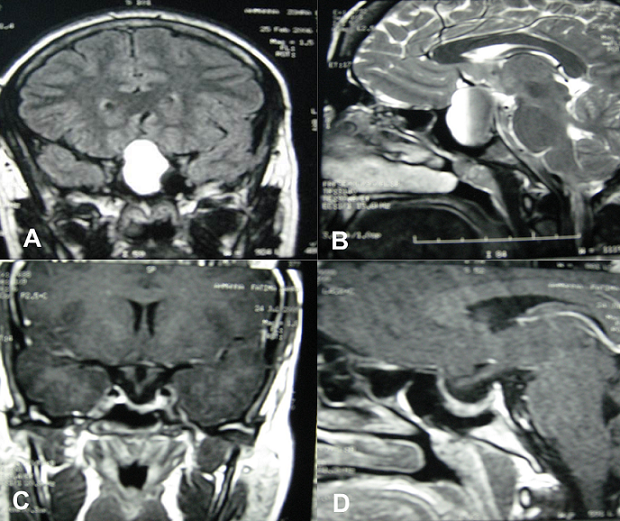

The pituitary apoplexy is a rare and fatal complication of the pituitary adenoma; it represents 0.6 to 10%. This is a clinical syndrome resulting from a fulminant pituitary expansion due to a bleeding and\or a pituitary infarcissement. We report the case of a 29-year-old patient who consults for an amenorrhoea with spontaneous galactorrhea and chronic headaches evolving over 7 months. The balance sheet of the amenorrhoea discovers a hyperprolactinemia in 224ng / ml treated by Bromocriptine without étiological survey. The patient had a pregnancy, and in 19 weeks of amenorrhoea, she presents of rough installation of the rebel headaches with visual disorders (blindness of the right eye). The magnetic resonance imaging (MRI) was in favour of a stroke of the pituitary macro-adenoma (A and B). The prolactin was always brought up. The patient was treated by Cabergoline. The evolution was favorable, with complete regression of the visual disorders after one month of treatment. The MRI of control shows the total disappearance of the leaving expansive process place in an intracellair arachnoidocèle (C and D). The clinical demonstrations of the pituitaire stroke are essentially represented by the tumoral syndrome, the visual disorders and the disorders of consciousness. The MRI is the examination of choice. In the case reported radiographic appearance was typical of a pituitary apoplexy.